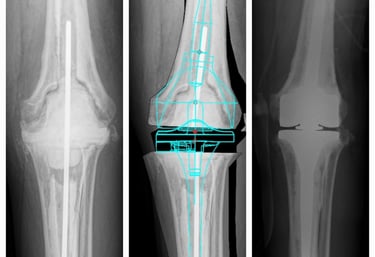

Cirugía de revisión de rodilla

Cirugía en la que se reemplaza la articulación dañada por una prótesis nueva. Se realiza en casos de desgaste severo, artrosis o lesiones que provocan dolor intenso y limitan la movilidad. El objetivo es devolver la capacidad de caminar, realizar actividades cotidianas sin dolor y mejorar la calidad de vida.

Prótesis de cadera y rodilla